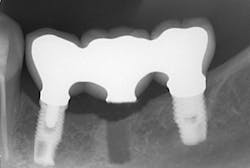

The same arguments have been advanced for not splinting adjacent implants in segmental reconstructions (figure 1). Plaque-related peri-implantitis is the most common biological complication in implant dentistry. A passive fit of prostheses on their supporting implants is considered essential for minimizing mechanical and biological overloading. On the other hand, it is also claimed that splinting can prevent overloading (figure 2). Screw loosening and fracture of veneering material are the most common mechanical complications of loading, although there is little evidence that it results in loss of integration.

Figure 2: Splinted adjacent implants